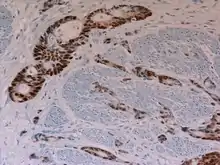

| Micrograph of urachal carcinoma (right of image) and non-malignant urothelium (left of image). H&E stain. | |

Histopathological Diagnosis

According to the current version (4th ed.) of the WHO classification of Tumours of the Urinary System, the diagnosis of a urachal adenocarcinoma usually needs a location of the tumor in the bladder dome and/or anterior wall, epicenter of the tumor in the bladder wall, absence of widespread cystitis cystica and/or cystitis glandularis beyond the dome or anterior wall, and absence of another similar structured tumor as a primary tumor elsewhere in the body. A urachal remnant in association with the tumor can help with the diagnosis.[10][11][12][13] In addition, other diagnostic systems also for urachal carcinomas that are not adenocarcinomas have been proposed.[14]

Immunohistochemical stains are usually less helpful in the histopathological differential diagnosis of urachal adenocarcinomas.[15]